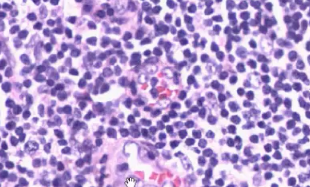

Starry sky appearence of the cortex in the thymus due to the presence of macrophages

Macrophages.

Most cell death occurs in the cortex of the thymus, macrophages carry out this function